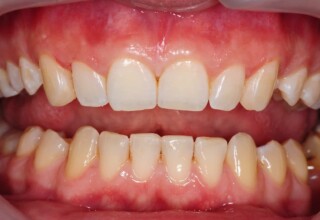

Restoration of bilateral diastemas between central and lateral incisors.

Diastemas were created mainly because of narrow laterals. After orthodontic treatment was finalized, the diastemas were closed with two composite resin restorations.